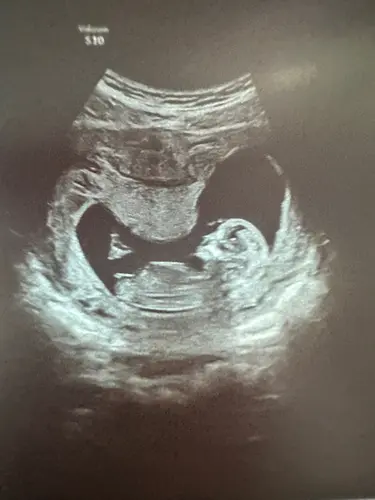

Wat denken jullie meisje of jongen?

We zullen het pas zeker weten bij de geboorte, maar mijn schoonzusje hield zich bezig met de theorieën en nu ben ik wel benieuwd wat anderen denken